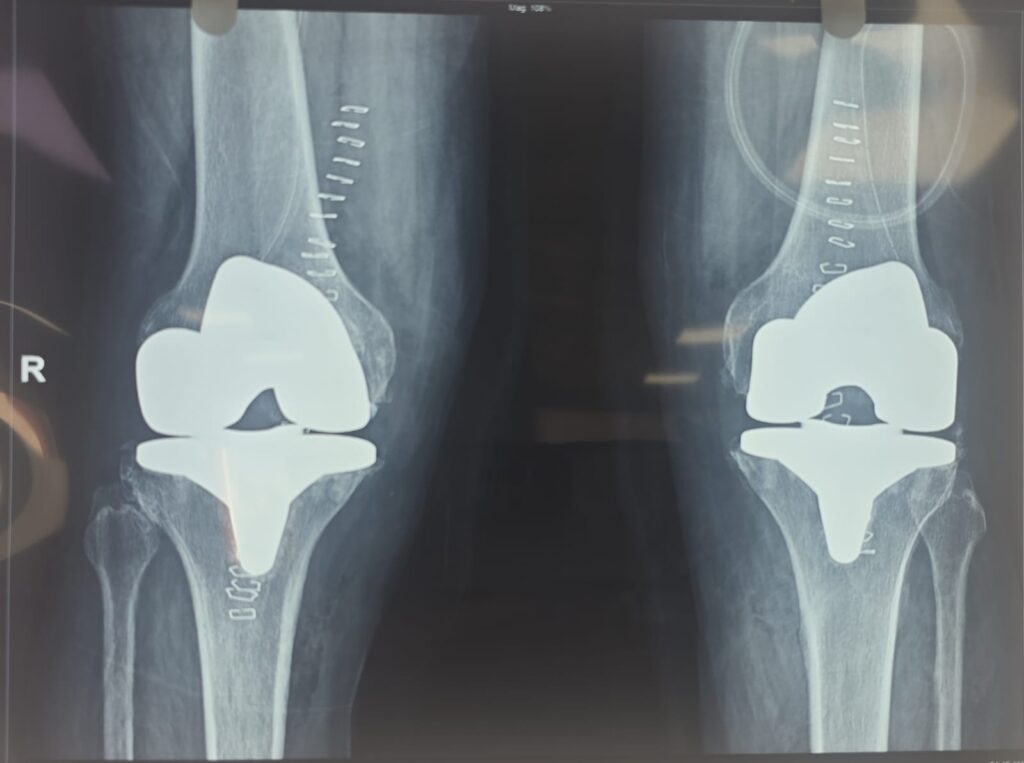

Joint Replacement

Advanced surgical care to replace damaged joints, relieving pain and restoring mobility with modern, minimally invasive and robotic techniques.